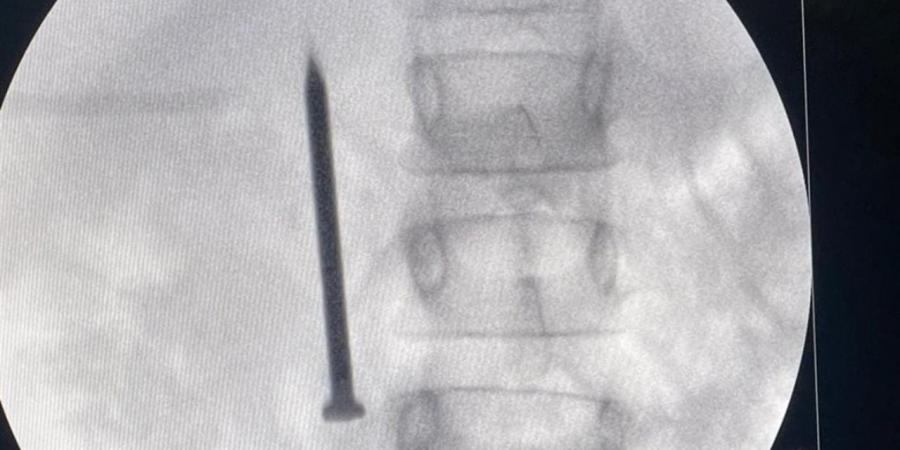

أعلن الدكتور أحمد القاصد، رئيس جامعة المنوفية، عن نجاح فريق طبي متخصص بوحدة مناظير الجهاز الهضمي بمعهد الكبد القومي في إنقاذ حياة طفلة تبلغ من العمر 7 سنوات، بعد ابتلاعها مسمارًا معدنيًا حادًا يبلغ طوله 4 سنتيمترات.

وأوضح رئيس الجامعة أن الفريق الطبي تمكن من استخراج المسمار الذي وصل إلى الجزء الأول من الأمعاء الدقيقة عبر إجراء منظار طارئ لم يستغرق سوى 20 دقيقة، متجنبًا بذلك خطر الثقب أو النزيف أو الانسداد المعوي الوشيك، حيث غادرت الطفلة المستشفى بصحة جيدة بعد التدخل الطبي السريع.

من جانبه، أكد الدكتور أحمد صيرة، أستاذ طب كبد الأطفال ورئيس وحدة مناظير الأطفال وقائد الفريق الطبي، أن استخدام المنظار كان الخيار الأمثل لتجنب إجراء عملية جراحية مفتوحة أكثر إرهاقًا للطفلة، مشددًا على أهمية التدخل السريع في مثل هذه الحالات لتفادي مضاعفات محتملة مثل الثقب أو النزيف أو الانسداد المعوي.